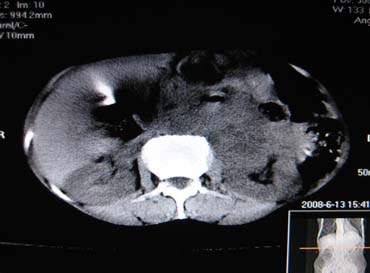

女,65岁,左上腹痛。

肝脏占位  脾脏及胰腺病变   请提供病史

肝脾胃左肾胰都显示不正常啊

病史不详,肝、脾、胰都有占位,谁是原发?

肝脏 脾脏 胰腺都有病变.

胰腺癌伴脾脏侵犯并肝内转移可能性大  建议增强扫描  否则没有确凿的依据

考虑姨尾癌,腹膜后转移\\肝转移

没有病史,没有强化,那就只有猜了,我看病灶很像肝、脾及腹腔多发脓肿,这只是我的意见,

图像欠清,病灶与胃脾胰肾上腺关系显示欠清,建议增强,肝脏考虑转移瘤.

多脏器占位,腹膜后淋巴结增大,淋巴瘤?建议增强扫描